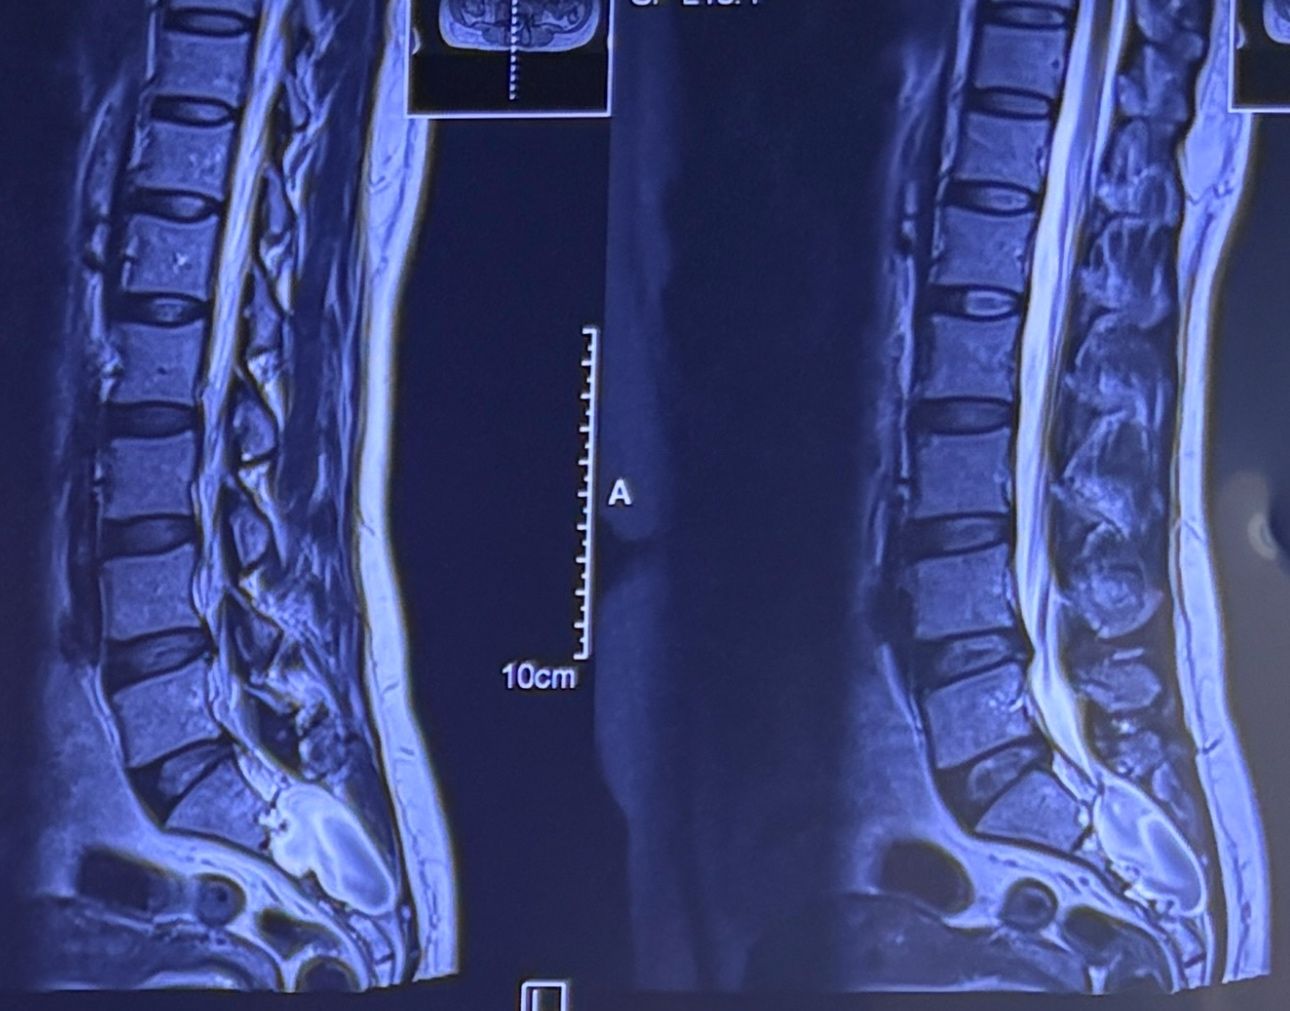

32 years female patient presented to my office one year ago with moderate cervical pain and R. Arm pain ,mild LBP with no radicular pain. Her mri in C/s had few bulges and few segmentsl dysfunctions

Her lumbar mri showed Contained R. Para. L5-S1 extrusion

She got treatment just for her neck and exercises for her low back. Few months later had lumbar disc surgery

Few days ago on may on june 08/2025, presented with severe LBP and no radicular pain

I have post her lumbar MRI before and after surgery. I consulted with a neurosurgeon at our clinic and he said doesn’t need another surgery because doesn’t have radicular pain or neurological deficits

For her pain i have started to do mild decompression by Cox and DTS and acupuncture, no adjustment whatsoever.

Please mention what differences you see before and after surgery